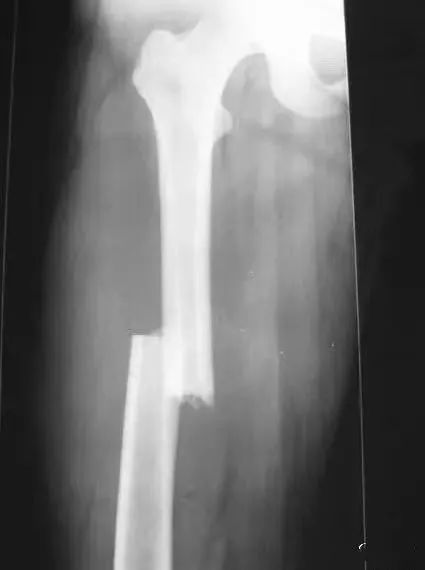

(3)股骨干骨折

股骨髁上骨折:股骨髁上处压痛敏锐、骨擦感和异常活动;X线片示髁上骨折。

(4)股骨髁上骨折

膝关节脱位:暴力强大,疼痛剧烈,肿胀严重,膝关节弹性固定在某一位置上,无骨擦音;X线可鉴别。